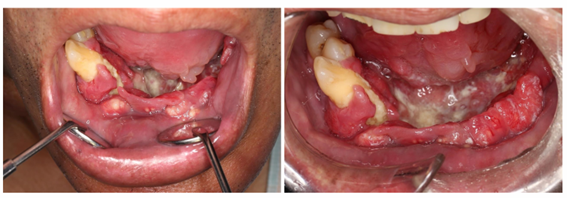

ホーム口腔疾患・症例について 口底がん 2025年8月28日2025年9月2日 口底癌は口腔癌の約10%を占め、口腔癌の中で最も多い舌癌と互いに浸潤することが多いです。写真のような進行癌では、食道癌、胃癌などの重複癌の場合もあります。 舌および下顎骨にも浸潤を認めるケースが多く、集学的治療が要求されます